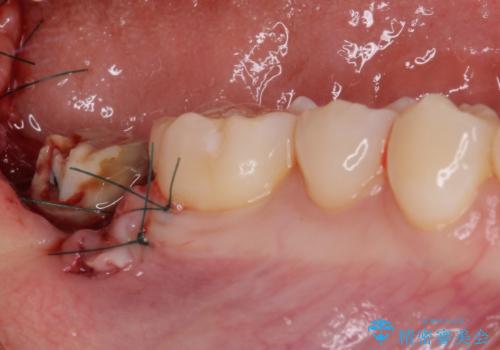

- 奥歯のかぶせものが頻繁に脱離することを気にされて来院された患者様です。

歯の高さが低く、かぶせものを安定して維持させることができないため、歯冠長延長術により歯の高さを増大させた上で、オールセラミッククラウンにて補綴することとしました。

クラウンが外れている期間も長く、虫歯が進行していたため、根管治療も行うこととしました。

- 外科手術のため、術後に出血、痛みや腫れ、違和感を伴います